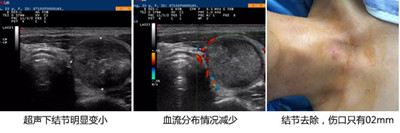

微创介入,一次性消除结节:超声引导,局部麻醉后将消融针穿刺入病灶组织进行消融,使其病变部位发生热固化,一次性将肿块细胞的活性完全消失。

2、不开刀,创伤小:不损伤周围血管、气管,伤口只有0.2mm,术后贴个创口贴。